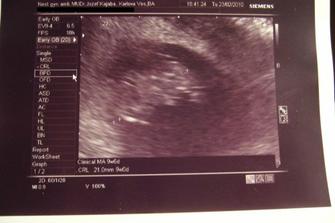

♥ 12.02.2010 sme boli na kontrolnom sone. Bábo zase krásne podrástlo a krásne mi zakývalo. Krvička nie je celkom v poriadku a čaká nás hematológia.